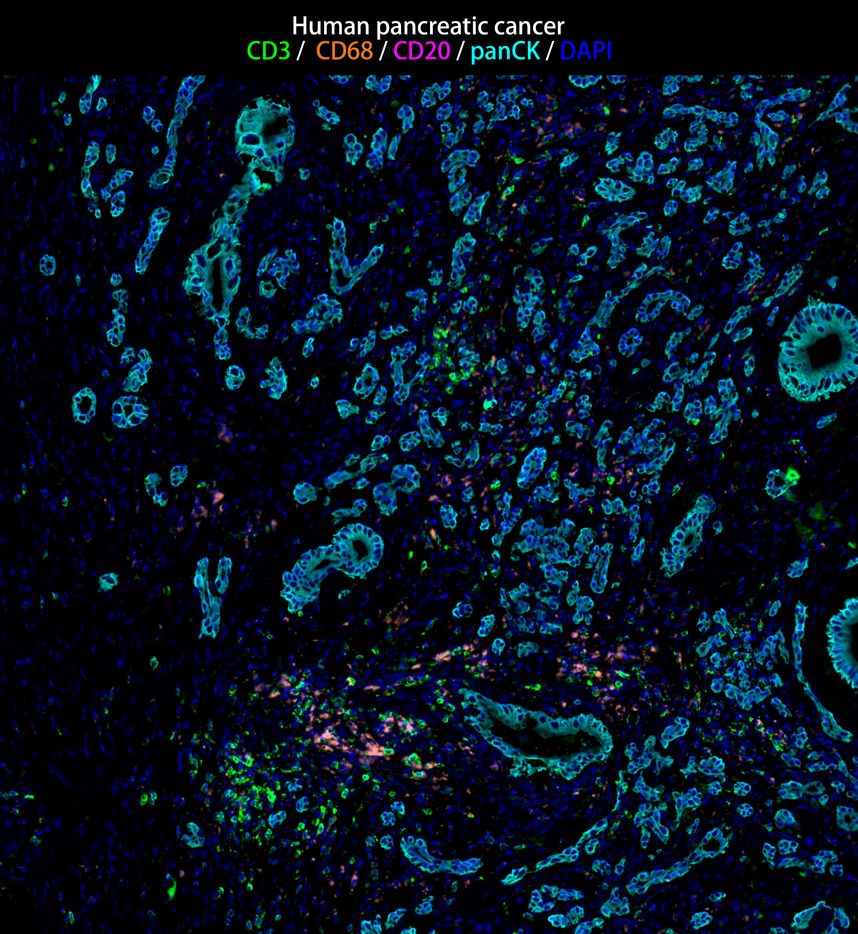

IRS003_7.jpg Fig7: mIHC analysis of human pancreatic cancer tissue (Formalin/PFA-fixed paraffin-embedded sections) with CD3, CD68 (IRS004), CD20 (IRS003) and panCK (IRS010) antibody at 1/100 dilution. The immunostaining was performed with the IRISKitCmTSA Kit (900802). Heat mediated antigen retrieval with Tris-EDTA buffer (pH 9.0) for 30 mins at 95℃. DAPI (blue) was used as a nuclear counter stain. Image acquisition was performed with Olympus VS200 Slide Scanner.